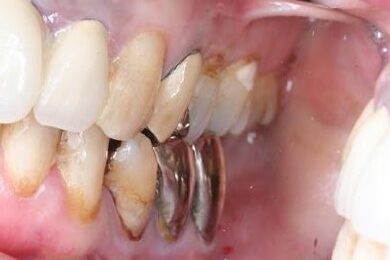

インプラントの症例写真 IMPLANT

インプラント治療+セラミック治療

| 治療内容 | インプラント3本、ジルコニアフレームオールセラミッククラウン7本(ジルコニア用土台1本)、メタルボンドセラミッククラウン3本(メタルボンド用土台3本)、ハイブリッドセラミッククラウン3本、ハイブリッドセラミックインレー3本 | ||||||||||||||||||||||||||||||||